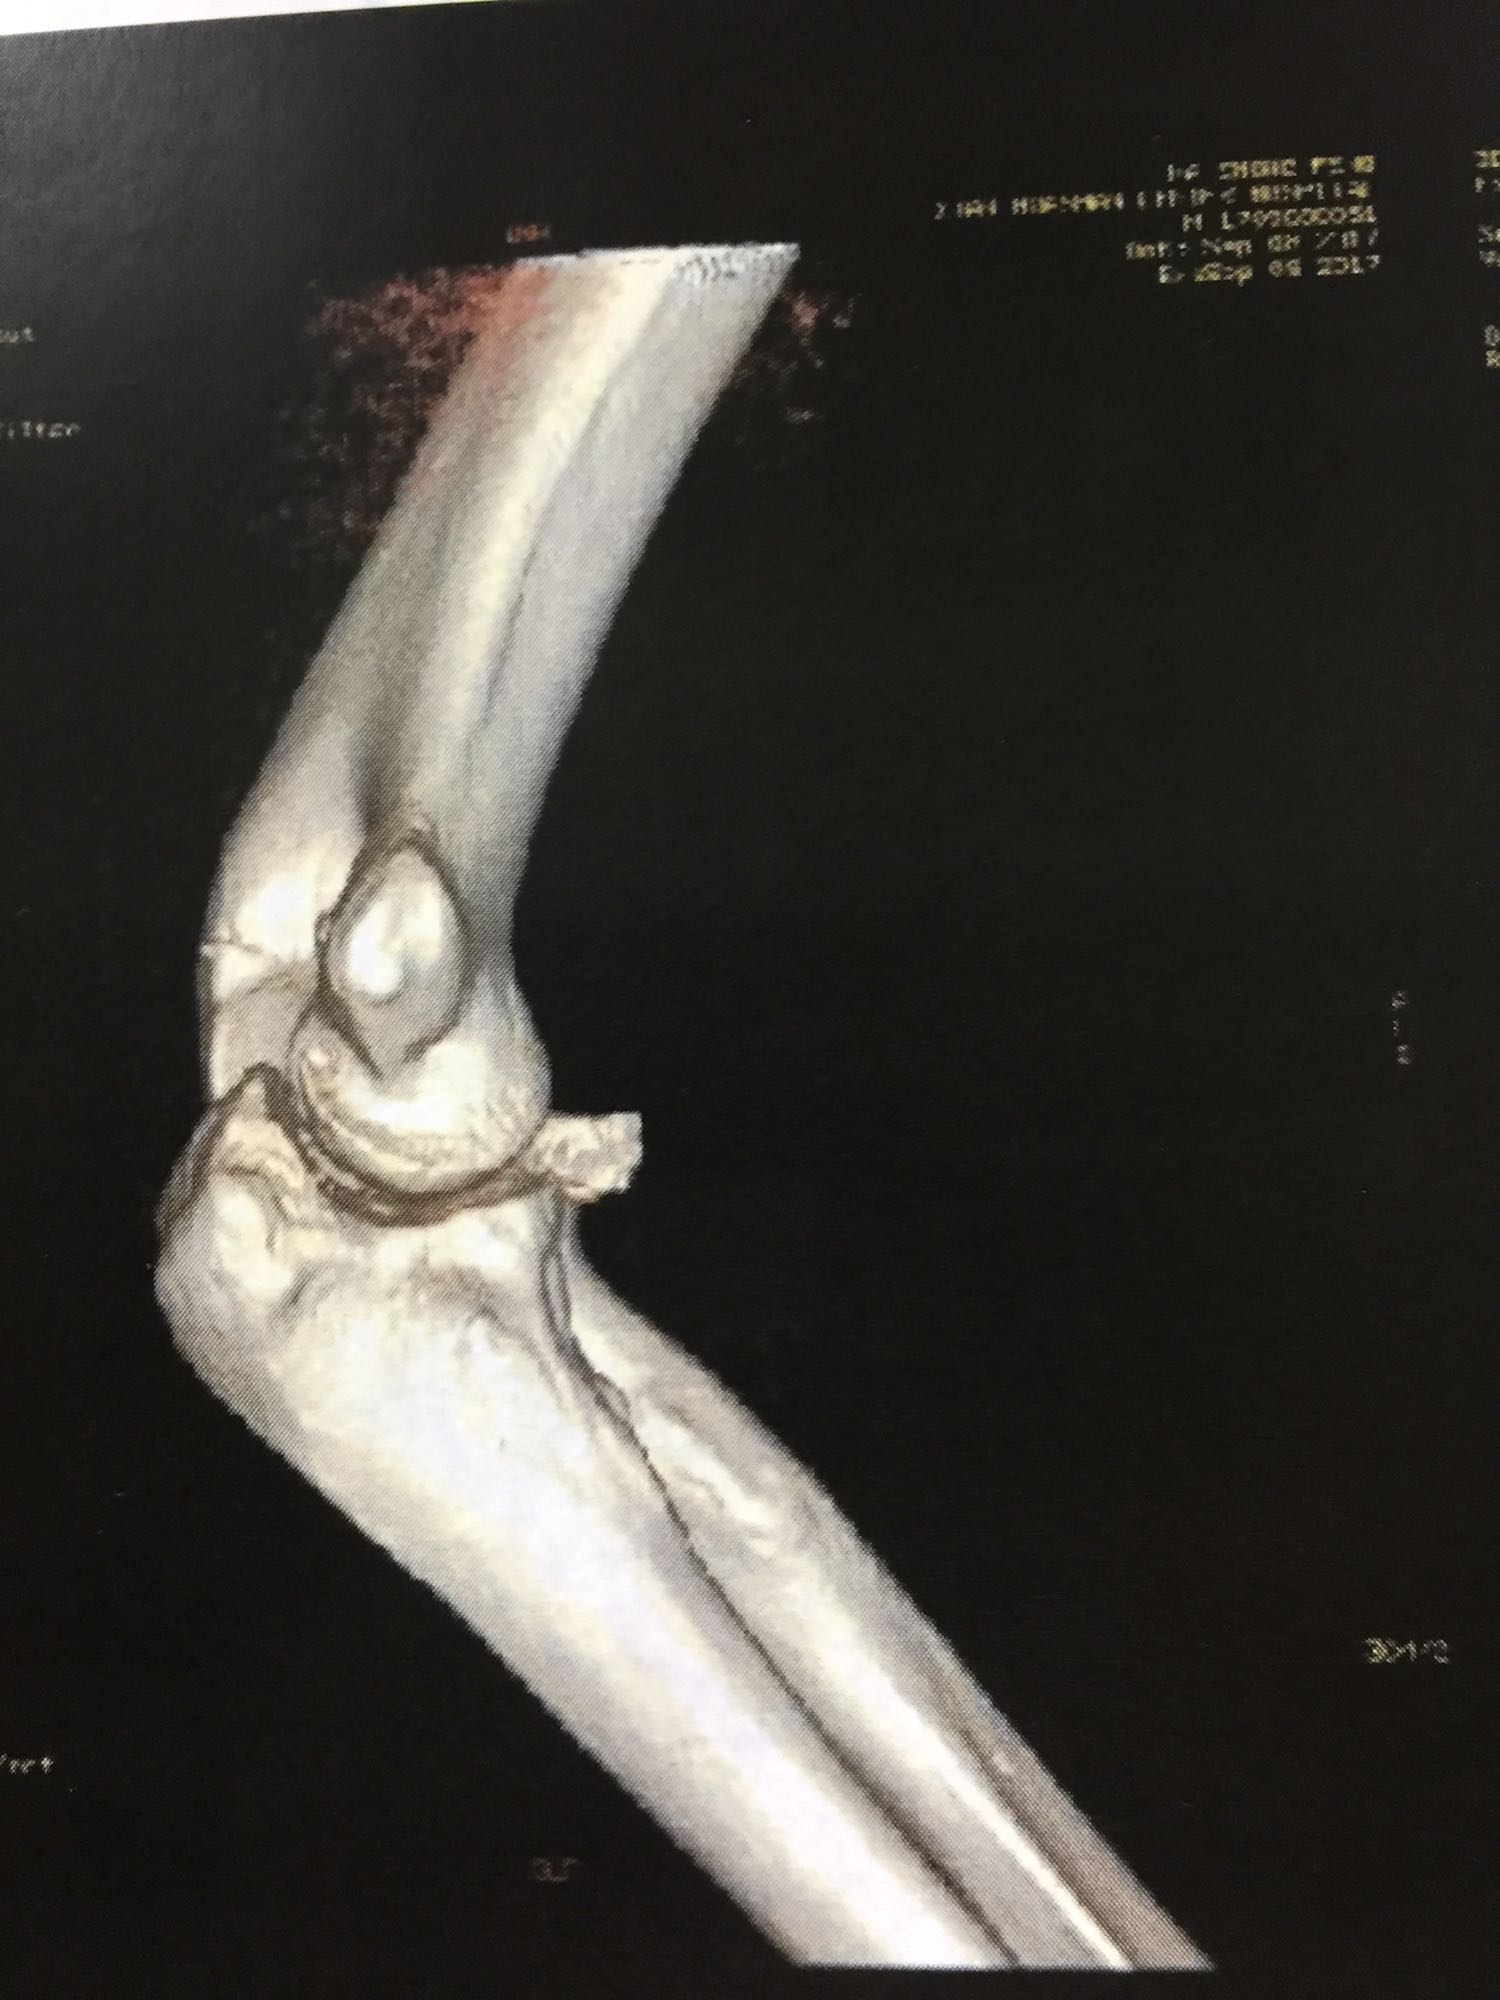

左肘关节高度肿胀,压痛强阳性,肘关节明显活动受限,末梢血运良好,各指关节运动正常。 X线片及CT如图:

1、左尺骨冠状突骨折;2、左肱骨外髁撕脱骨折 治疗:入院后伤肢石膏外固定,给予局部冷敷消肿治疗,于伤后一周行骨折手术治疗,先行前内侧切口复位固定冠状突骨折,活动肘关节发现关节明显不稳定,随取外侧切口,复位固定肱骨外髁,修补外侧副韧带,肘关节明显稳定。术中术后片子如下